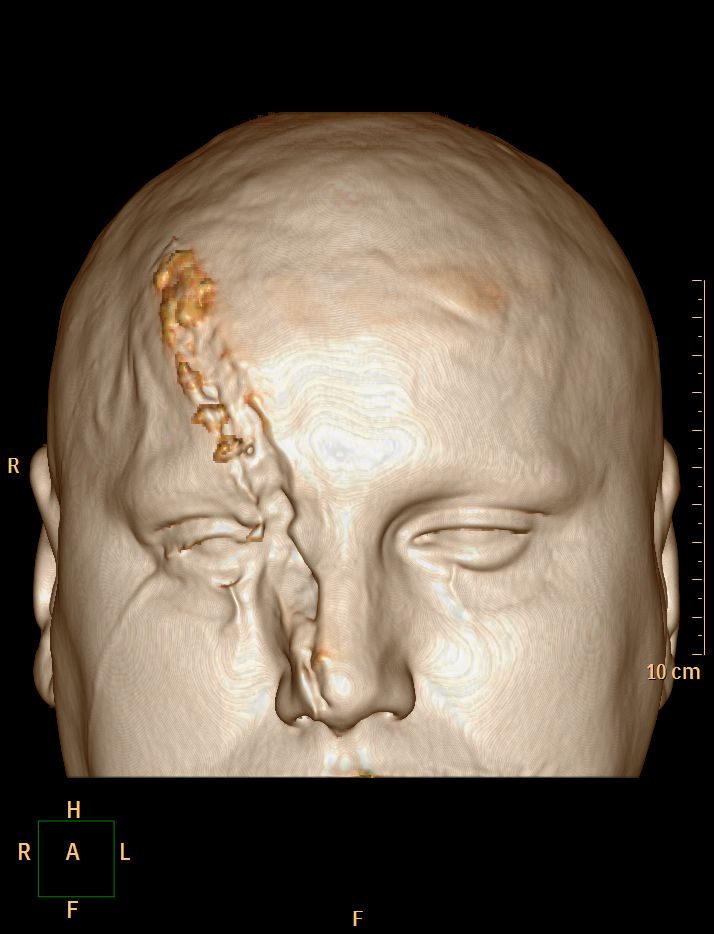

Accident de scie circulaire